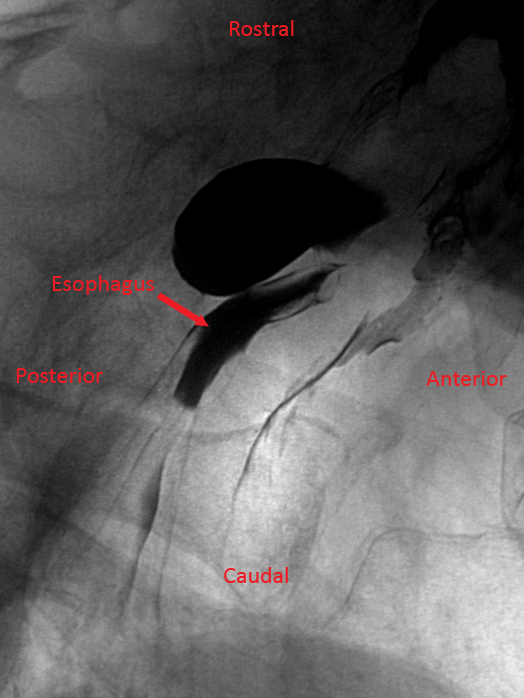

A 74-year-old man comes to the office due to several months of choking spells, dysphagia, and cough.  He has also had recurrent episodes of pneumonia.  His other medical problems include hypertension and osteoarthritis.  Blood pressure is 130/70 mm Hg.  The patient has foul-smelling breath, but his oropharyngeal and neck examinations are normal.  Cardiopulmonary examination is also normal.  A barium swallow study is performed and reveals an abnormality in the upper esophagus, as shown in the image below. A 74-year-old man comes to the office due to several months of choking spells, dysphagia, and cough.  He has also had recurrent episodes of pneumonia.  His other medical problems include hypertension and osteoarthritis.  Blood pressure is 130/70 mm Hg.  The patient has foul-smelling breath, but his oropharyngeal and neck examinations are normal.  Cardiopulmonary examination is also normal.  A barium swallow study is performed and reveals an abnormality in the upper esophagus, as shown in the image below.   Which of the following mechanisms is the most likely cause of his symptoms? A) Cricopharyngeal motor dysfunction B) Degenerative changes of the myenteric plexus C) Increased intraluminal pressure in the stomach D) Retention cyst due to duct obstruction E) Scarring and traction of the esophagus Which of the following mechanisms is the most likely cause of his symptoms?